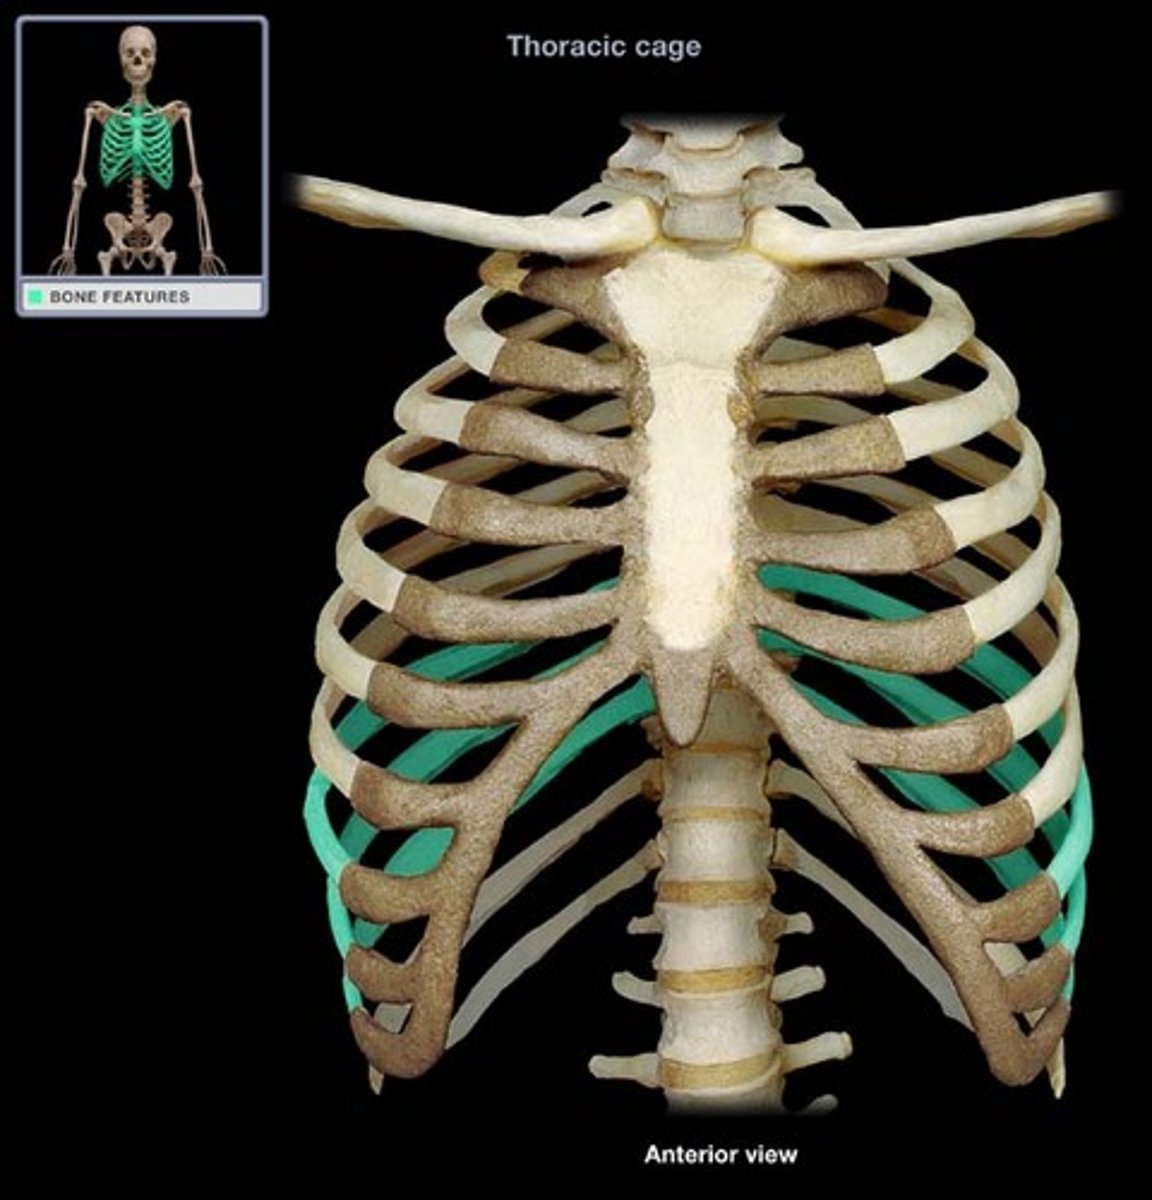

External Intercostals

What is this muscle?

true ribs

1-7

false ribs

8-12

floating ribs

11-12

costal cartilages

What is this structure?